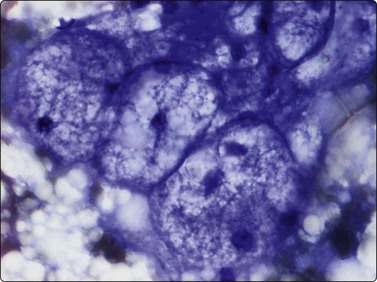

Myxoid liposarcoma, the commonest of the liposarcomas is currently divided in two variants: paucicellular and hypercellular myxoid liposarcoma. Paucicellular myxoid liposarcoma is identical with the classic myxoid liposarcoma, while the hypercellular variant corresponds to the former round cell liposarcoma. The reason to rename round cell liposarcoma is that this subtype was found to express the same chromosomal aberration, t(12;16)(q13;p11), as classic myxoid liposarcoma.10 In paucicellular myxoid liposarcoma, the peculiar network of anastomosing capillary vessels is well recognisable in FNB smears and is one of three characteristic features. The other two are abundant myxoid background matrix and slightly atypical lipoblasts. Smears consist mainly of small tissue fragments with branching capillary vessels embedded in the myxoid matrix (Fig. 15.28A). The tumor cells, mainly seen in the fragments, have spindle or ovoid, relatively uniform nuclei and a thin cytoplasm. Lipoblasts are always found – uni- or multivacuolated with scalloped nuclei (Fig. 15.28B). The lipoblasts are best visualised in MGG; the cytoplasmic vacuoles are less prominent in H&E. Differentiation from low-grade malignant myxofibrosarcoma (MFS) depends on the demonstration of the capillary network within the tumor fragments and of lipoblasts. The vessel fragments seen in smears of MFS are usually thicker and are present in the myxoid ground substance. Smears of hypercellular myxoid liposarcoma (former round cell liposarcoma) show either numerous dissociated cells or tissue fragments containing closely packed tumor cells. The fragments are considerably more cellular than those of the paucicellular type; myxoid ground substance is less conspicuous and the capillary network less prominent. The tumor cells have irregular, rounded nuclei and a malignant chromatin pattern. The cytoplasm is fragile and many nuclei are stripped. Mitotic figures are occasionally seen and atypical lipoblasts always found.

Fig. 15.28 Myxoid liposarcoma

(A) Tissue fragment of cells embedded in myxoid background material; typical anastomosing vessels (MGG, IP); (B) Scattered multivacuolated lipoblasts (MGG, HP).